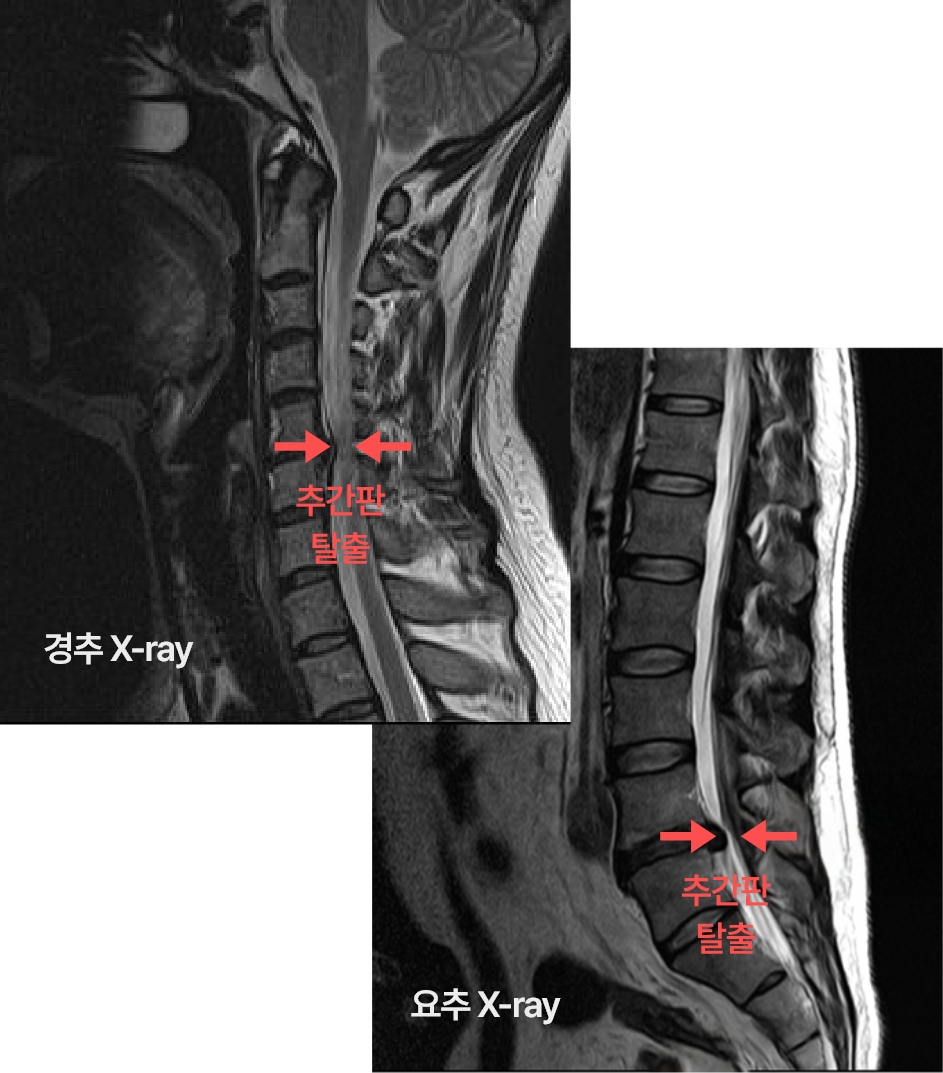

경추/요추 디스크

경추/요추 디스크 질환은 주로 목(경추)이나 허리(요추) 부위에서

발생하며, 척추 뼈 사이의 추간판이 탈출하거나 손상되어 주변

신경을 압박함으로써 통증을 유발합니다.

X-ray 검사 CT, MRI 검사

디스크 돌출 및 신경 압박 상태 확인

경막외 신경주사, 도수치료, 체외충격파, 물리치료, 추나치료

그 외 신경성형술, 수핵성형술도 많이 시행